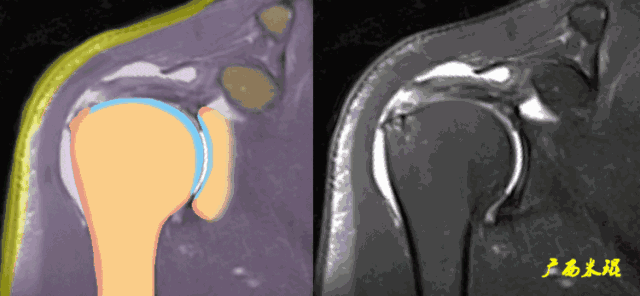

c、钩状肩峰,发生肩袖撕裂的机会大,但绝不是百分之百。

d、肩峰骨刺,发生肩袖撕裂的机会比钩状肩峰还要大,必须认真阅看,肩峰骨刺在斜矢状位上显示得非常清楚。

肩峰骨刺在斜冠状位上能够看到,应该认真观察并且留意其对应的肩袖面。